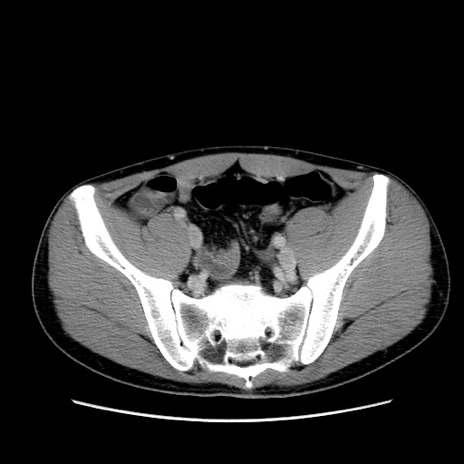

症例36(横断像)

【症例】20歳代 男性

【主訴】心窩部痛

【現病歴】今朝より上腹部痛あり。一旦軽快していたが再度出現したため救急要請。昨日夕に白身の魚を含む刺身を食べた。

【身体所見】BP 136/89mmHg、HR 74/min、BT 37.0℃、腹部:膨満、軟、心窩部に圧痛あり。反跳痛なし、筋性防御なし、腸雑音やや亢進あり。

【データ】WBC 17700、CRP 0.48